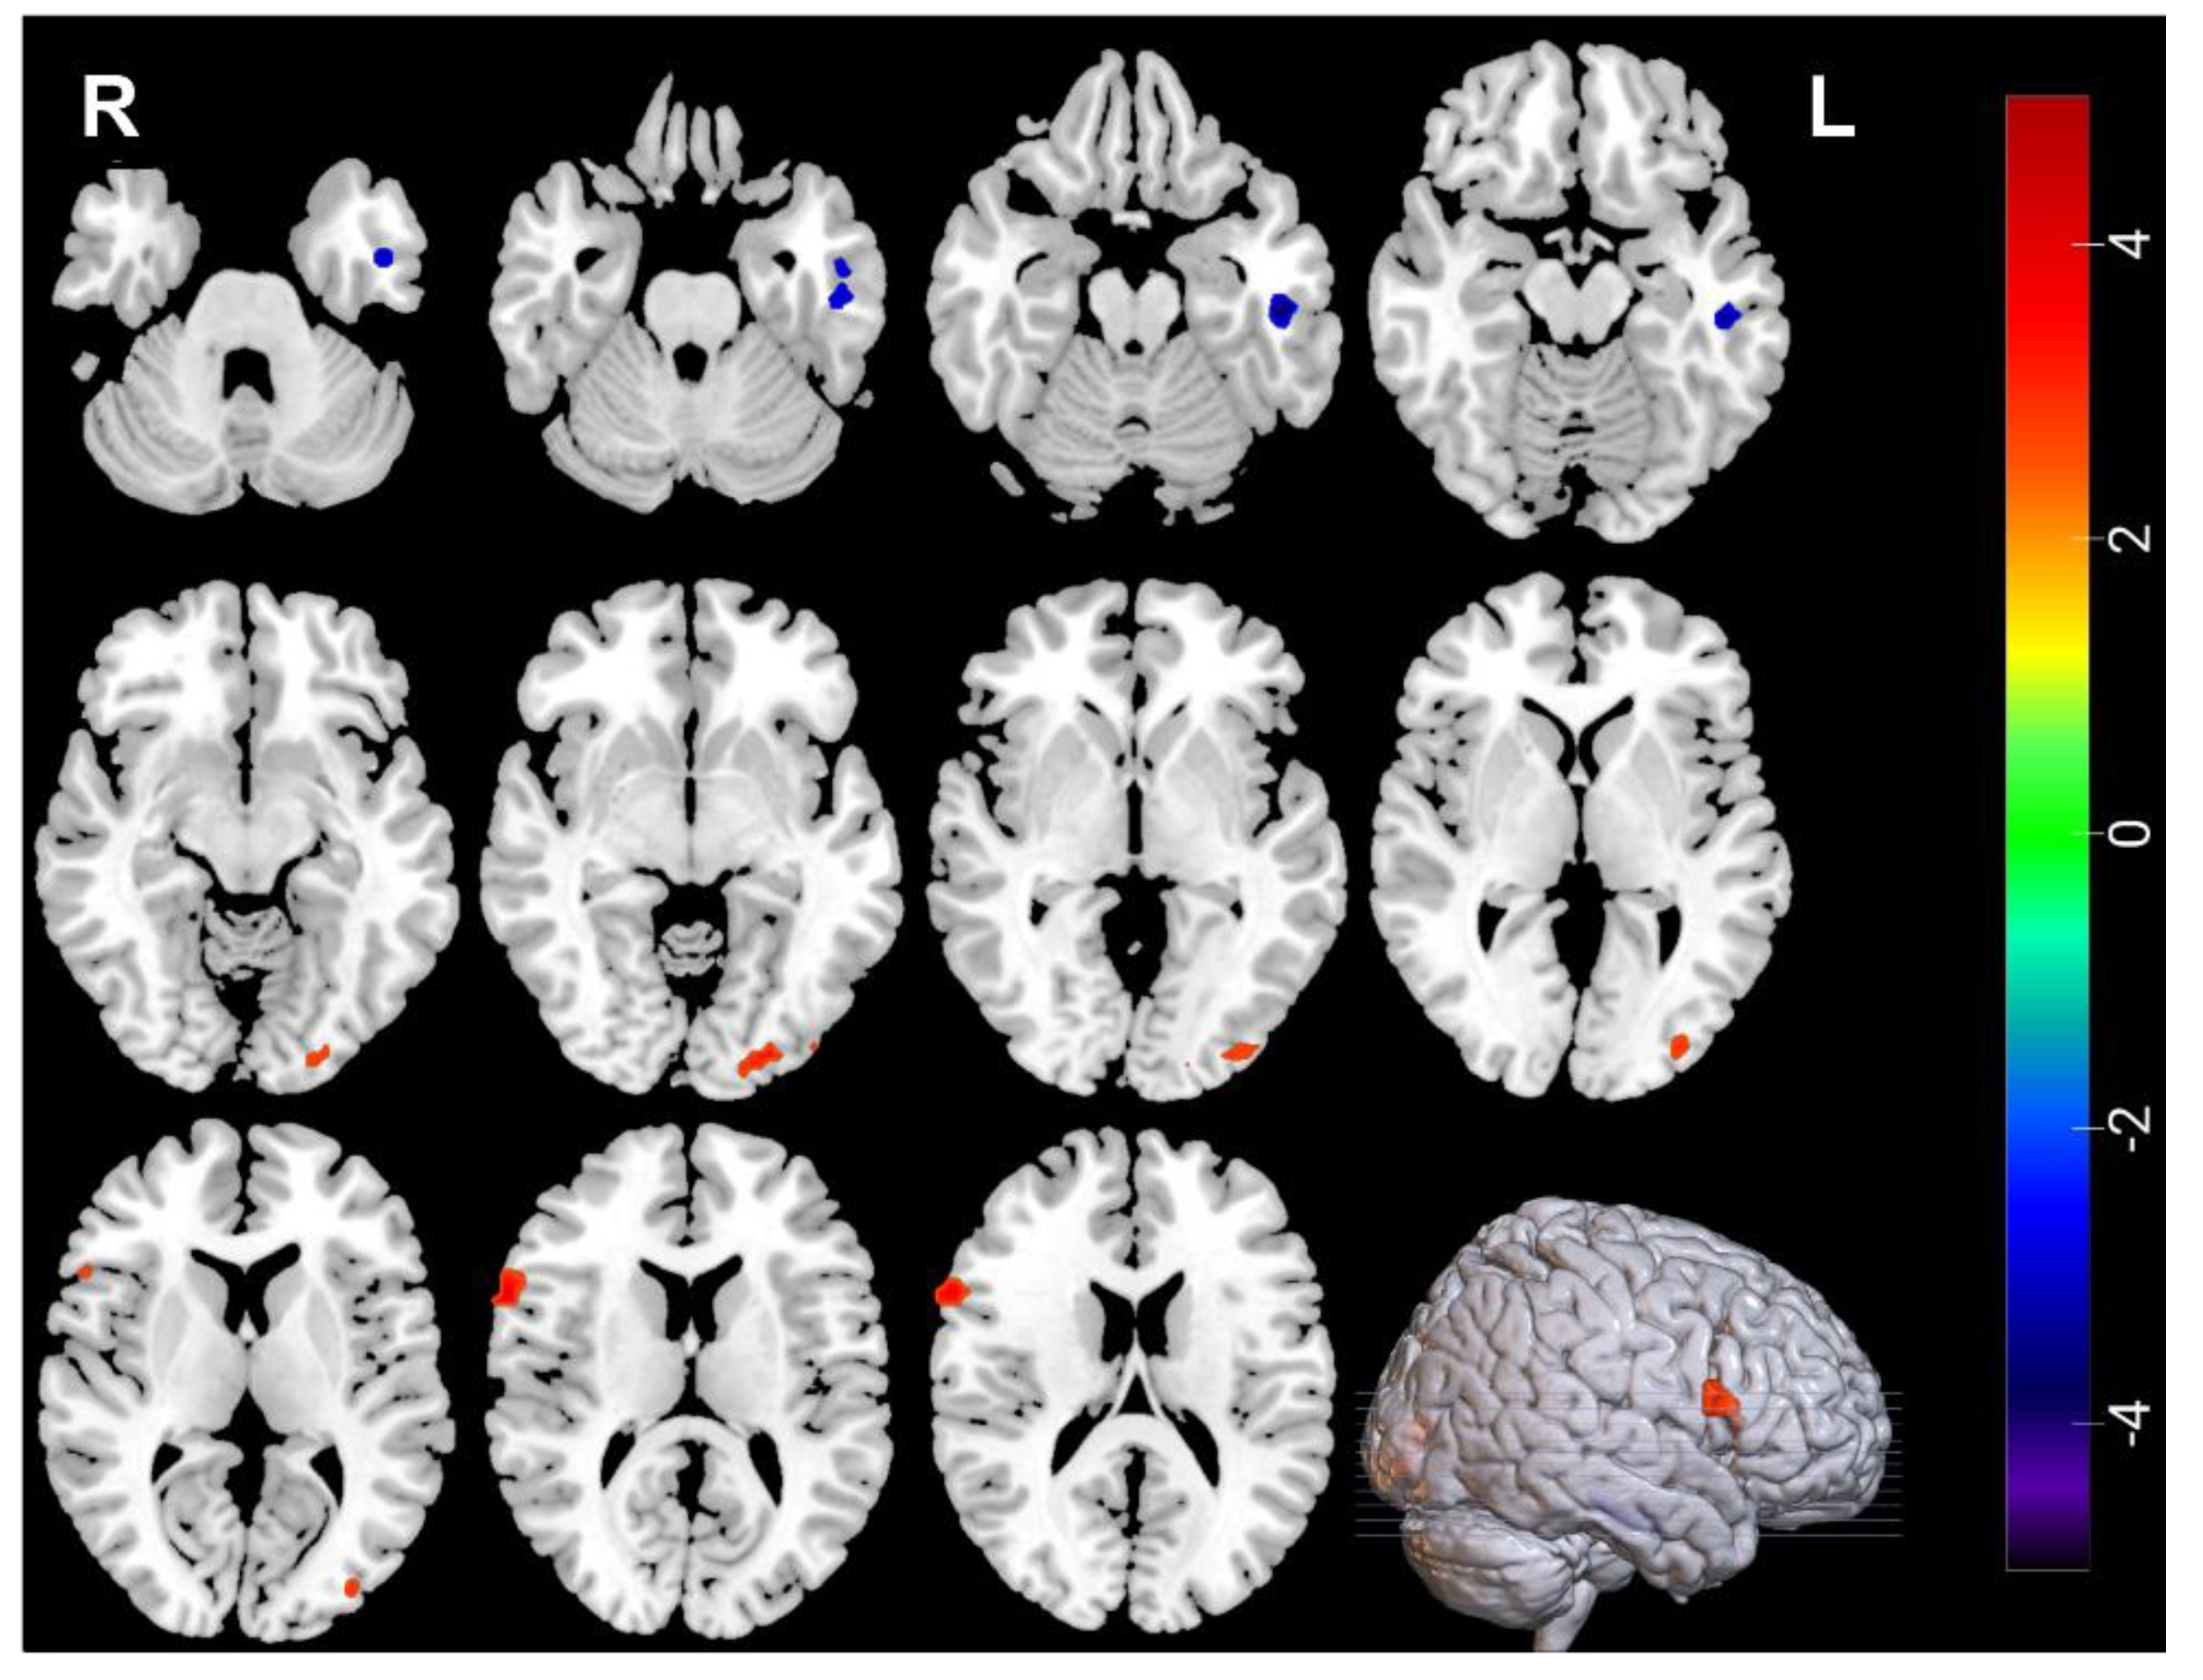

3.3. Neuroimaging Comparisons in MDDs Pre/Post-ECT

| Measures | Brain Regions | Voxel Size | Peak t Value | MNI Coordinates | ||

|---|---|---|---|---|---|---|

| Decreased | ||||||

| ALFF | Temporal_Pole_Sup_L | 30 | −4.0615 | −51 | 18 | −15 |

| ALFF | Frontal_Inf_Oper_L | 39 | −3.9169 | −54 | 12 | 12 |

| ALFF | Frontal_Mid_R | 34 | −4.2384 | 42 | −3 | 51 |

| Increased | ||||||

| ALFF | Occipital_Mid_R | 30 | 3.7765 | 42 | −66 | 24 |

| ReHo | Occipital_Mid_R | 46 | 4.5719 | 42 | −63 | 24 |

| ReHo | Temporal_Inf_L | 38 | 4.761 | −51 | −3 | −33 |